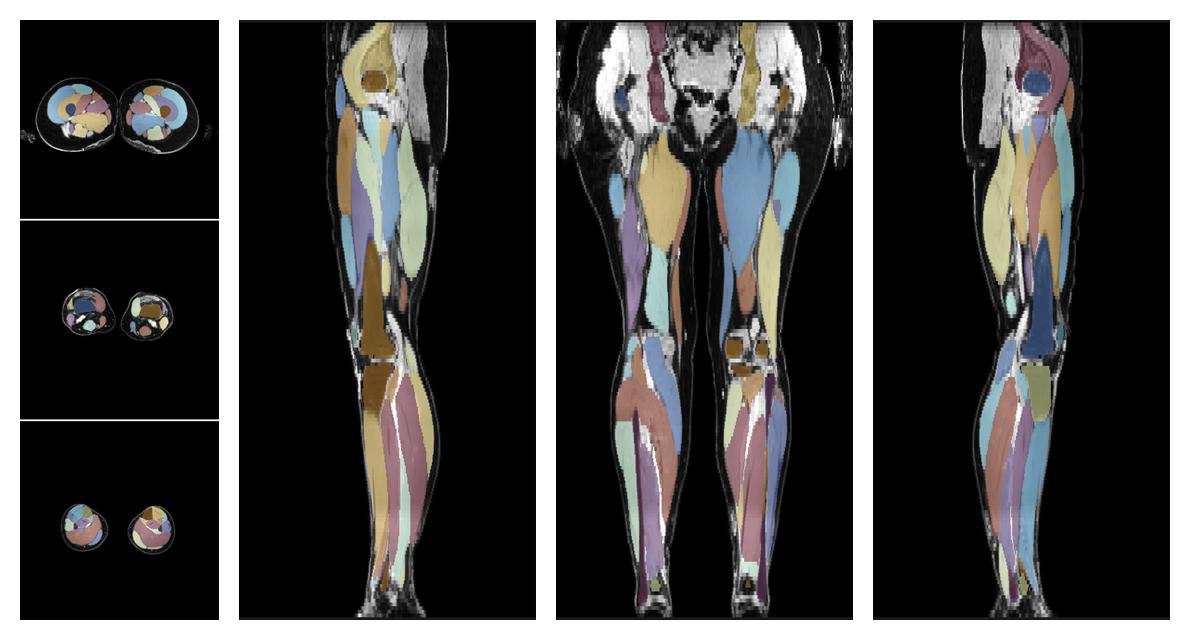

• Automated muscle and bone segmentation.

Overlay of automated muscle segmentation labels on dixon water image.